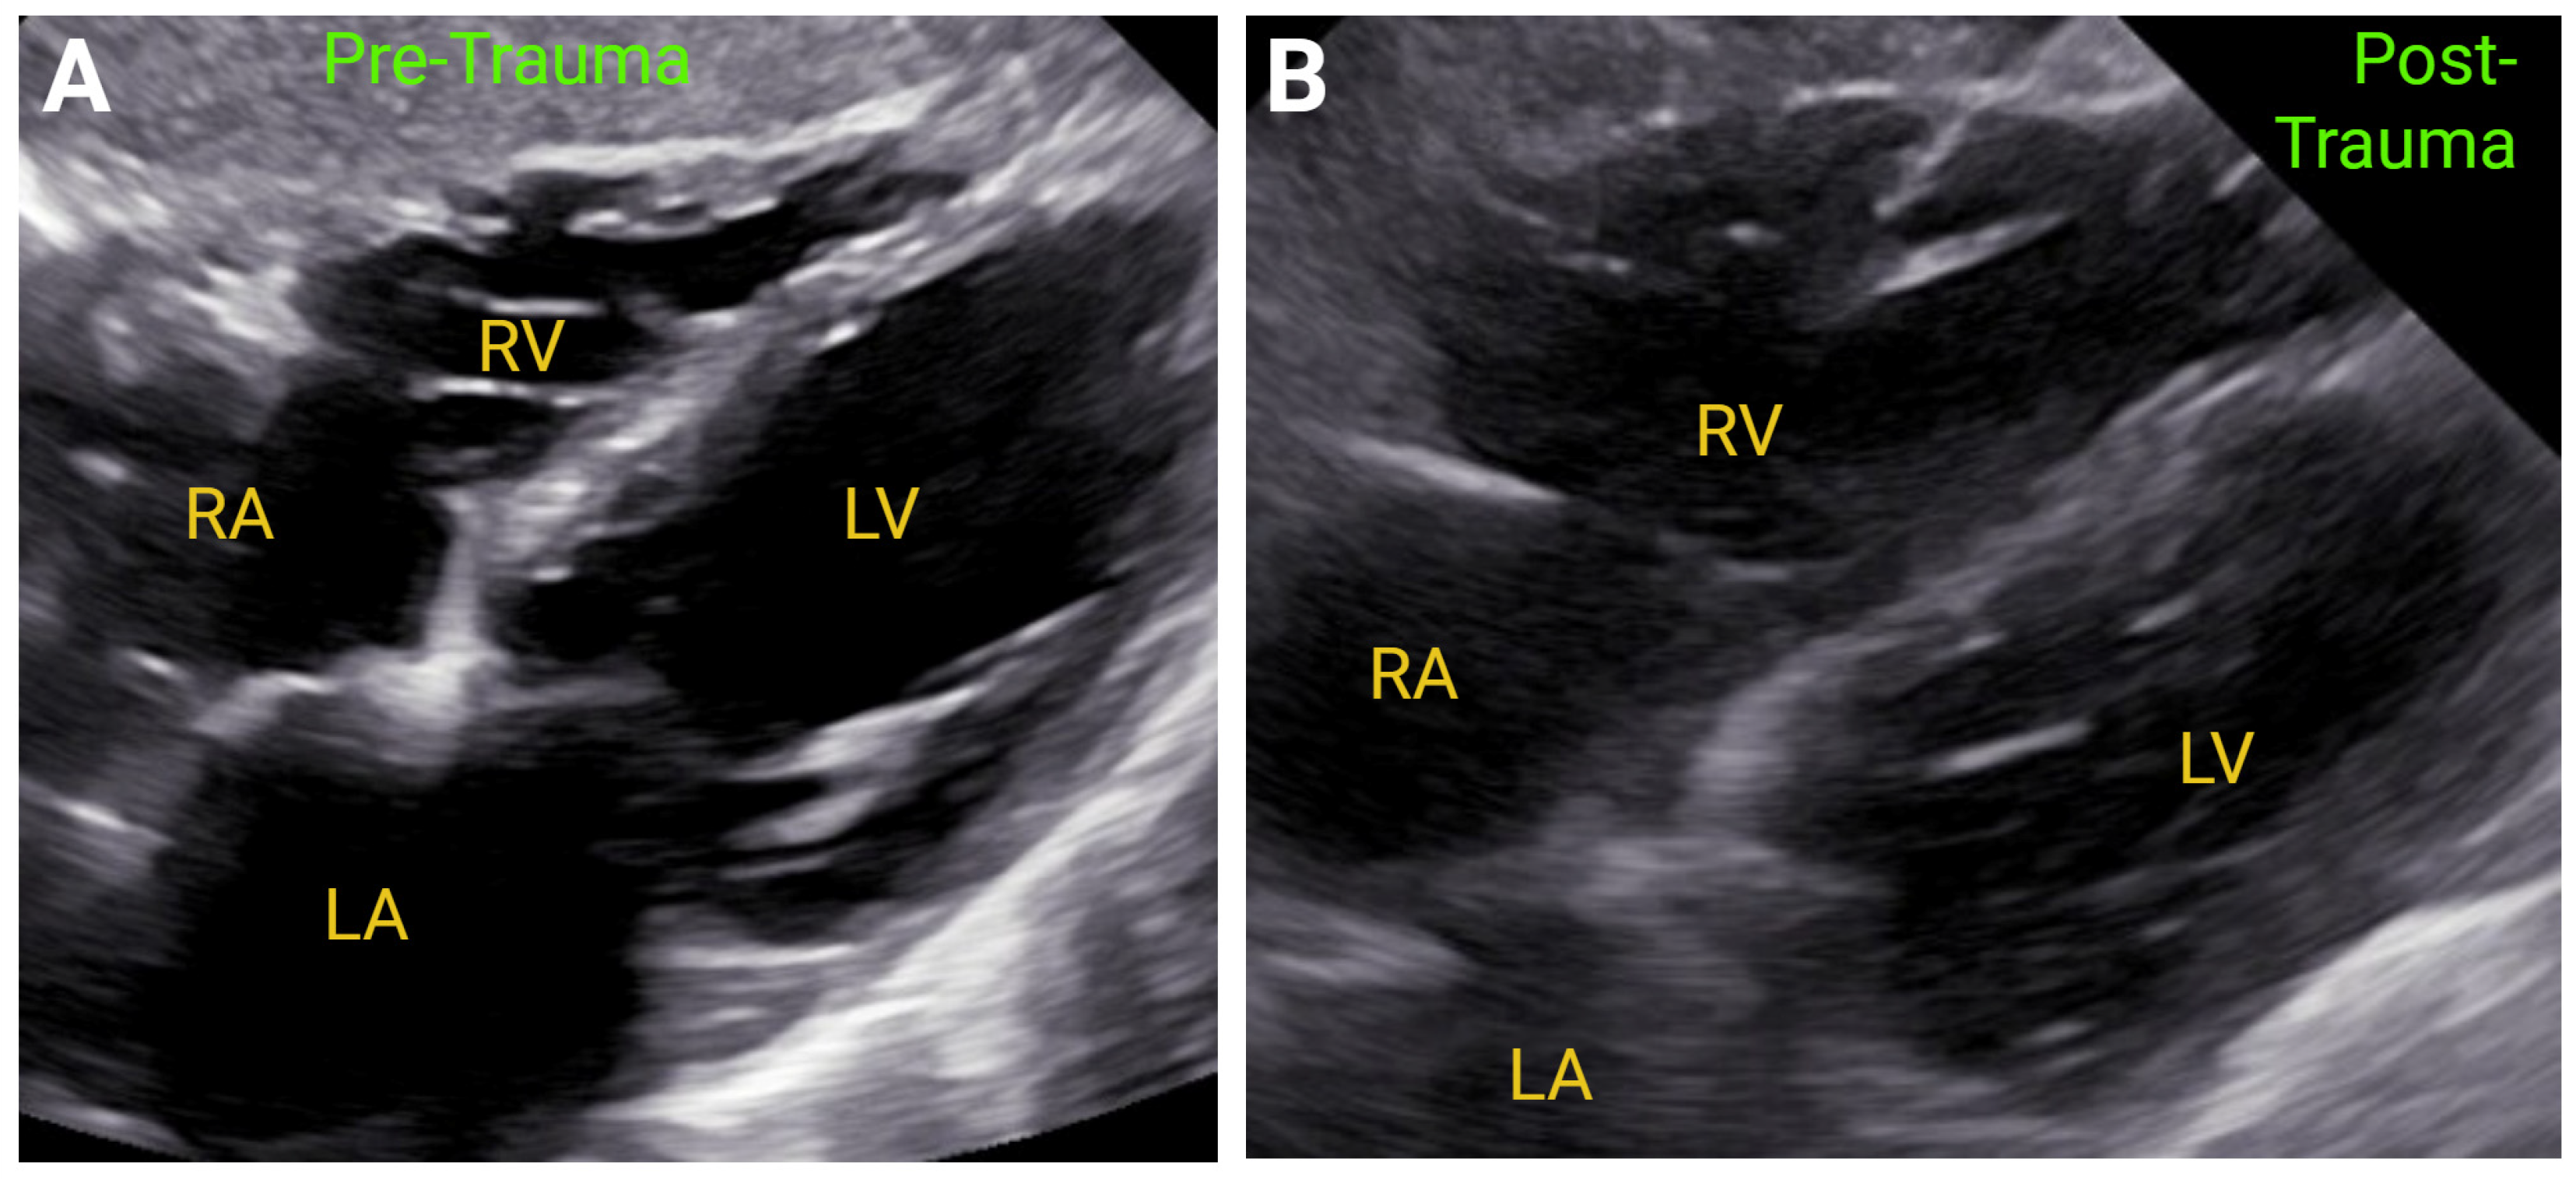

7.1. Acute Right-Sided Heart Failure

- Pretre, R.; Chilcott, M. Blunt trauma to the heart and great vessels. N. Engl. J. Med. 1997, 336, 626–632. [Google Scholar] [CrossRef] [PubMed]

- Garcia-Fernandez, M.A.; Lopez-Perez, J.M.; Perez-Castellano, N.; Quero, L.F.; Virgos-Lamela, A.; Otero-Ferreiro, A.; Lasara, A.M.; Vega, M.; Moreno, M.; Pastor-Benavent, J.A.; et al. Role of transesophageal echocardiography in the assessment of patients with blunt chest trauma: Correlation of echocardiographic findings with the electrocardiogram and creatine kinase monoclonal antibody measurements. Am. Heart J. 1998, 135, 476–481. [Google Scholar] [CrossRef] [PubMed]